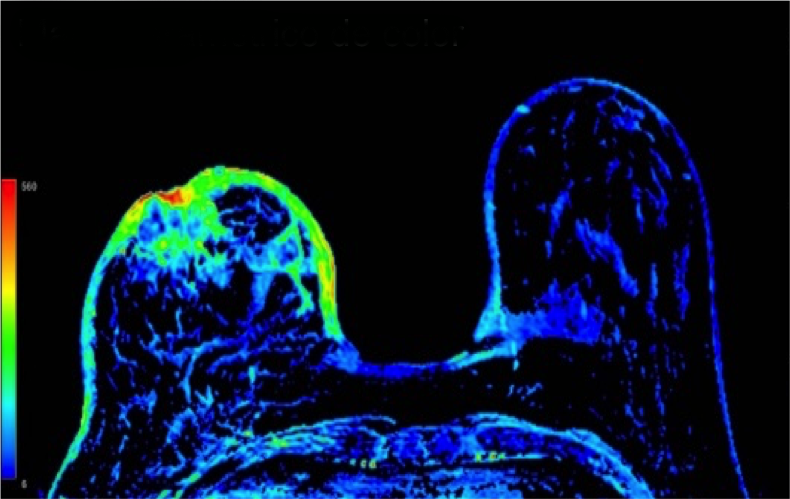

2. Describe los hallazgos por RM:

- C. Engrosamiento cutáneo en CCII de MD con realce heterogéneo nodular asociado a un realce tipo no masa retroareolar con curvas funcionales sospechosas (tipo 2).